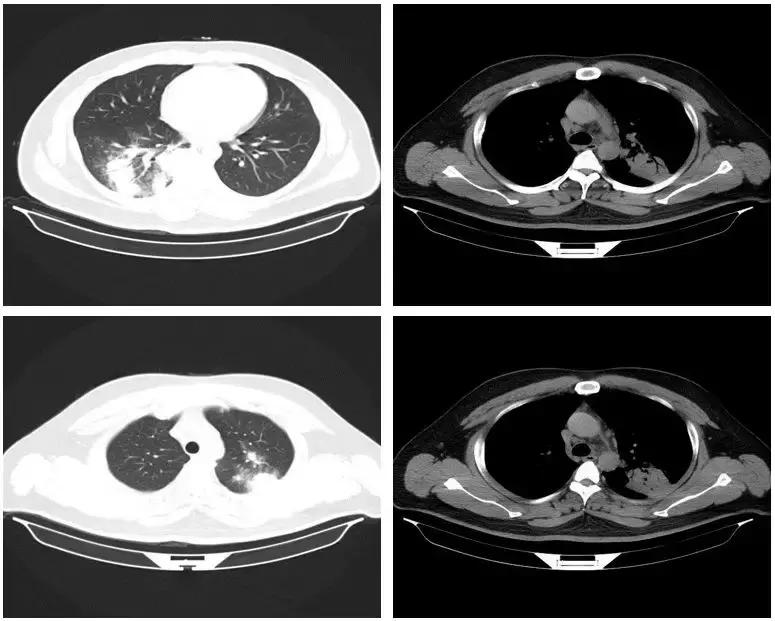

从影像学来说,空洞在肺曲霉病中更常见

实变及胸腔积液在肺念珠菌病中更常见

念珠菌感染的影像学缺乏特异性

念珠菌感染的影像学表现

念珠菌感染很容易累及到胸膜,而PCP往往是以磨玻璃样的两肺间质改变、有时有囊腔样改变,胸膜少有累及。

从影像学我们可以看到,双肺类似实变样改变,一般会考虑为细菌性肺炎,但仔细看CT可发现在实变中有空洞的改变,周围有些晕征的改变,而且抗细菌治疗无好转,此时需要考虑是不是治疗未覆盖真正的病原体。